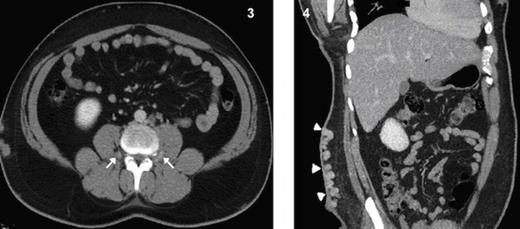

Dilated and tortuous azygous & hemiazygous veins (Fig. 2), with multiple prevertebral and paravertebral collaterals (Fig. 3) as well as superificial collateral veins in the abdominal wall (Fig. 4) were seen. Left renal vein is draining into the hypoplastic segment of IVC (Fig. 5).

Axial CT image shows collateralization of paraspinal veins (arrows) Fig 4. Coronal MPR CT image shows massive varices of superficial collateral veins at the abdominal wall.